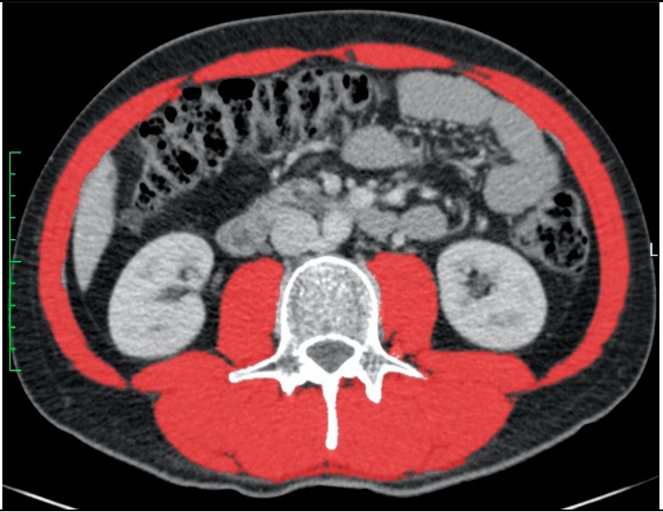

3.2. Diagnosis of Low Muscle Mass in Two Selected Patients

![]() | ![]() | All male patients (n = 118) * | |

| Sex | Male | Male | Male |

| Age (years) | 51 | 31 | 63.6 (51.4–71.3) |

| Height (cm) | 160 | 197 | 177.1 ± 7.3 |

| Weight (kg) | 93 | 85 | 79.1 ± 14.0 |

| BMI (kg/m2) | 36.3 | 21.9 | 25.2 ± 4.4 |

| CT area (cm2) | 939.8 | 592.4 | 749.8 ± 187.6 |

| A: Diagnosis of low or normal muscle mass according to sex-specific cut-offs set at the mean of our study population | |||

| SMA (cm2) | 150.6 (normal) | 162.9 (normal) | 148.3 ± 23.7 |

| SMA/height2 (cm2/m2) | 58.8 (normal) | 42.0 (low) | 47.3 ± 7.6 |

| SMA/BMI (cm2/(kg/m2)) | 4.1 (low) | 7.4 (normal) | 6.0 ± 1.0 |

| B: Diagnosis of low or normal muscle mass according to published cut-offs for low muscle mass | |||

| Derstine, 2018: SMA by sex [8] | Normal | Normal | |

| Derstine, 2018: SMA/height2 by sex [8] | Normal | Low | |

| Mourtzakis, 2008: SMA/height2 by sex [13] | Normal | Low | |

| Prado, 2008: SMA/height2 by sex [17] | Normal | Low | |

| Martin, 2013: SMA/height2 by sex and BMI [3] | Normal | Low | |

| Martin, 2018: SMA/height2 by sex and age [16] | Normal | Low | |

| van der Werf, 2018: SMA by sex, age and BMI [10] | Low | Normal | |

| van der Werf, 2018: SMA/height2 by sex, age and BMI [10] | Normal | Normal | |

| Tanaka, 2020: SMA/BMI by sex [9] | Low | Normal | |